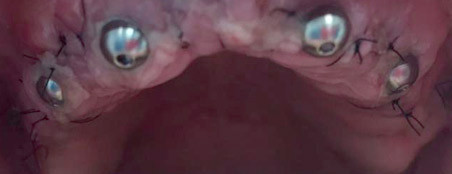

Имплантация All-on-4

Имплантация All-On-4 делит жизнь наших пациентов на до и после✨

Работа выполнена нашими специалистами: врач-стоматолог-имплантолог Гусейнов Ариф Эскендарович и врач-стоматолог-ортопед Архипов Андрей Евгеньевич

Имплантация All-on-4

Пациентка 48 лет. Исходно тяжелый пародонтит. Состояние старых протезов неудовлетворительное. Технология «Всё на 4-х» (установлено всего по 4 имплантата на каждой челюсти). Металлокомпозитные несъемные конструкции.

Имплантация All-on-4

Пожилая дама с годами утратила зубы на верхней челюсти и обратилась за протезированием на имплантатах. По состоянию челюстной кости ей подошел метод All-on-4 (Всё-на-четырёх), когда для фиксации протеза достаточно 4 имплантатов. На фото временный протез из акрила Vertex. Через полгода запланирована установка постоянной конструкции.

Доктор: Ветренко Виктория Александровна

Имплантация All-on-4

Имплантация All-On-4 делит жизнь наших пациентов на до и после✨

Работа выполнена нашими специалистами: врач-стоматолог-имплантолог Гусейнов Ариф Эскендарович и врач-стоматолог-ортопед Архипов Андрей Евгеньевич